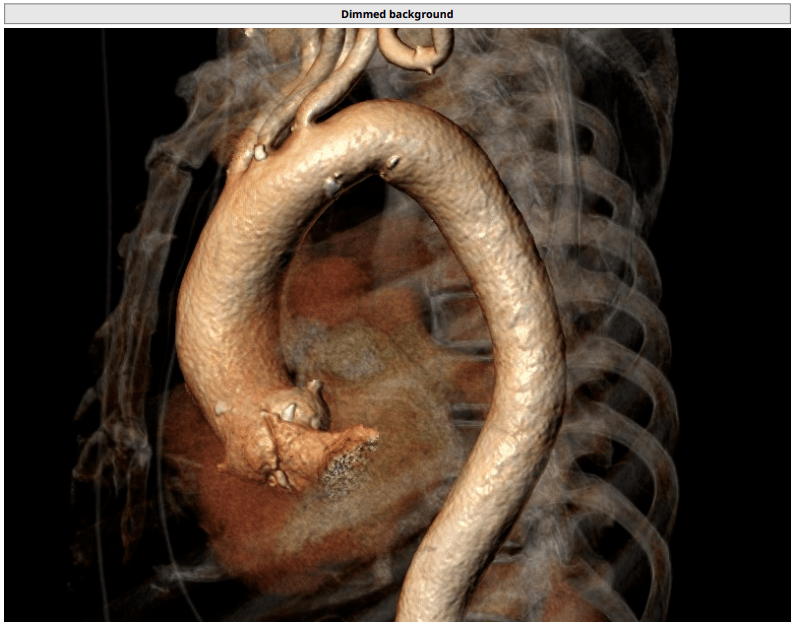

治疗团队发现她的大动脉在胸腹动脉连接段有严重的钙化和缩窄,导致她

包块原来是"巨大腹主动脉瘤,双侧髂动脉瘤,瘤体近端远端扭曲钙化严重"

不太大但超级难的腹主动脉瘤

男子腰腹部疼痛,原来是长了复杂性罕见巨大腹主动脉瘤